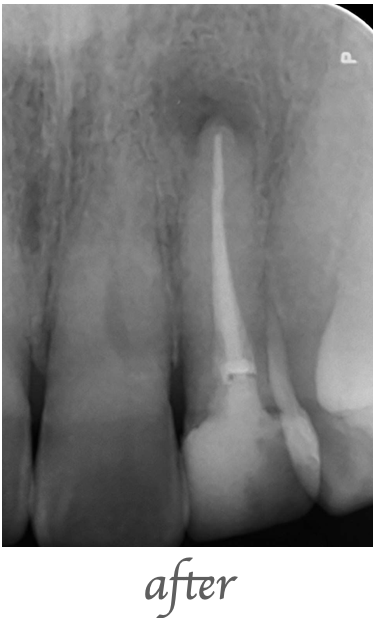

治療内容

レントゲンで左上の前歯の根の先に大きな病巣が見つかったため、精密根管治療を行いました。ラバーダムを行い、歯科用顕微鏡(マイクロスコープ)、ニッケルチタンファイル、MTAセメントを使用し根管充填を行いました。

治療期間・回数

治療期間:約2週間 治療回数:2回

費用

¥70,000(税込77,000)

リスク・副作用

治療直後に軽微な痛みが出ることがあります。根尖病巣の再発、症状改善が認められない場合があります。